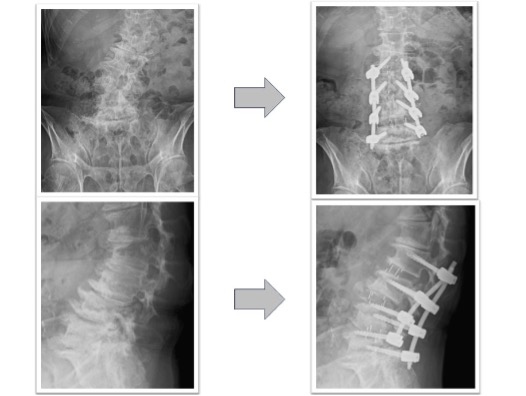

腰椎固定術実例(OLIF症例、*患者様の許可を得て掲載しています)

椎間板ヘルニア(図1)

体動困難を伴う激烈な下肢痛に対してL4/5の固定術を実施。術前に認められていたL4/5の椎間板ヘルニアがOLIFによる固定術後、間接除圧効果などによって消失しています(図1、赤丸)。レントゲンでは椎間ケージと腰椎L4とL5を固定する椎弓根スクリューが確認できます(図1、下段)。本症例の傷は左わき腹に4-5cmと、背部のスクリュー刺入部位に2㎝弱の傷が4つとなります。術後、痛みは消失しました。

図1

腰椎すべり症+椎間板ヘルニア(図2)

下肢痛で来院し歩行困難のため手術となりました。術前認められていたL3/4の椎間板ヘルニアがOLIFによる固定術後消失(赤丸)、またL4/5に認められていた変性すべり症による椎体のずれ、不安定性も術後は元の脊椎の並びに矯正された状態で固定されています(黄丸)。術後は症状消失し、元通り歩行可能となりました。

図2